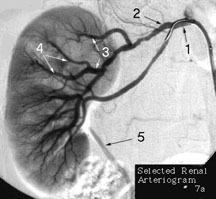

Arteries are prone to numerous disease processes, but the most common pathology is atherosclerosis, also know as hardening of the arteries. This disease causes the inside of arteries to narrow due to the build up of deposits that, over the years, begin to mineralize and harden. Note the moderate narrowing of the renal artery immediately after number 2 in the above image.

This image of the right kidney is a renal arteriogram. Note the placement of the catheter in the renal artery (#1). Number 5 is the urteter, which is seen because the contrast that was injected through the catheter, has already passed through the filtration system of the kidney, and is heading for the bladder.

#2. Proximal subdivion of renal artery

#3. Segmental renal arteries

#4. Interlobar arteries